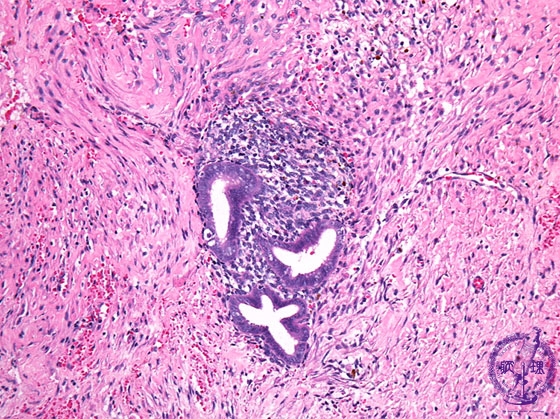

- ★(2)Endometriosis

Histology (HE stain, intermediate power): Ectopic endometrial tissue in cyst wall.